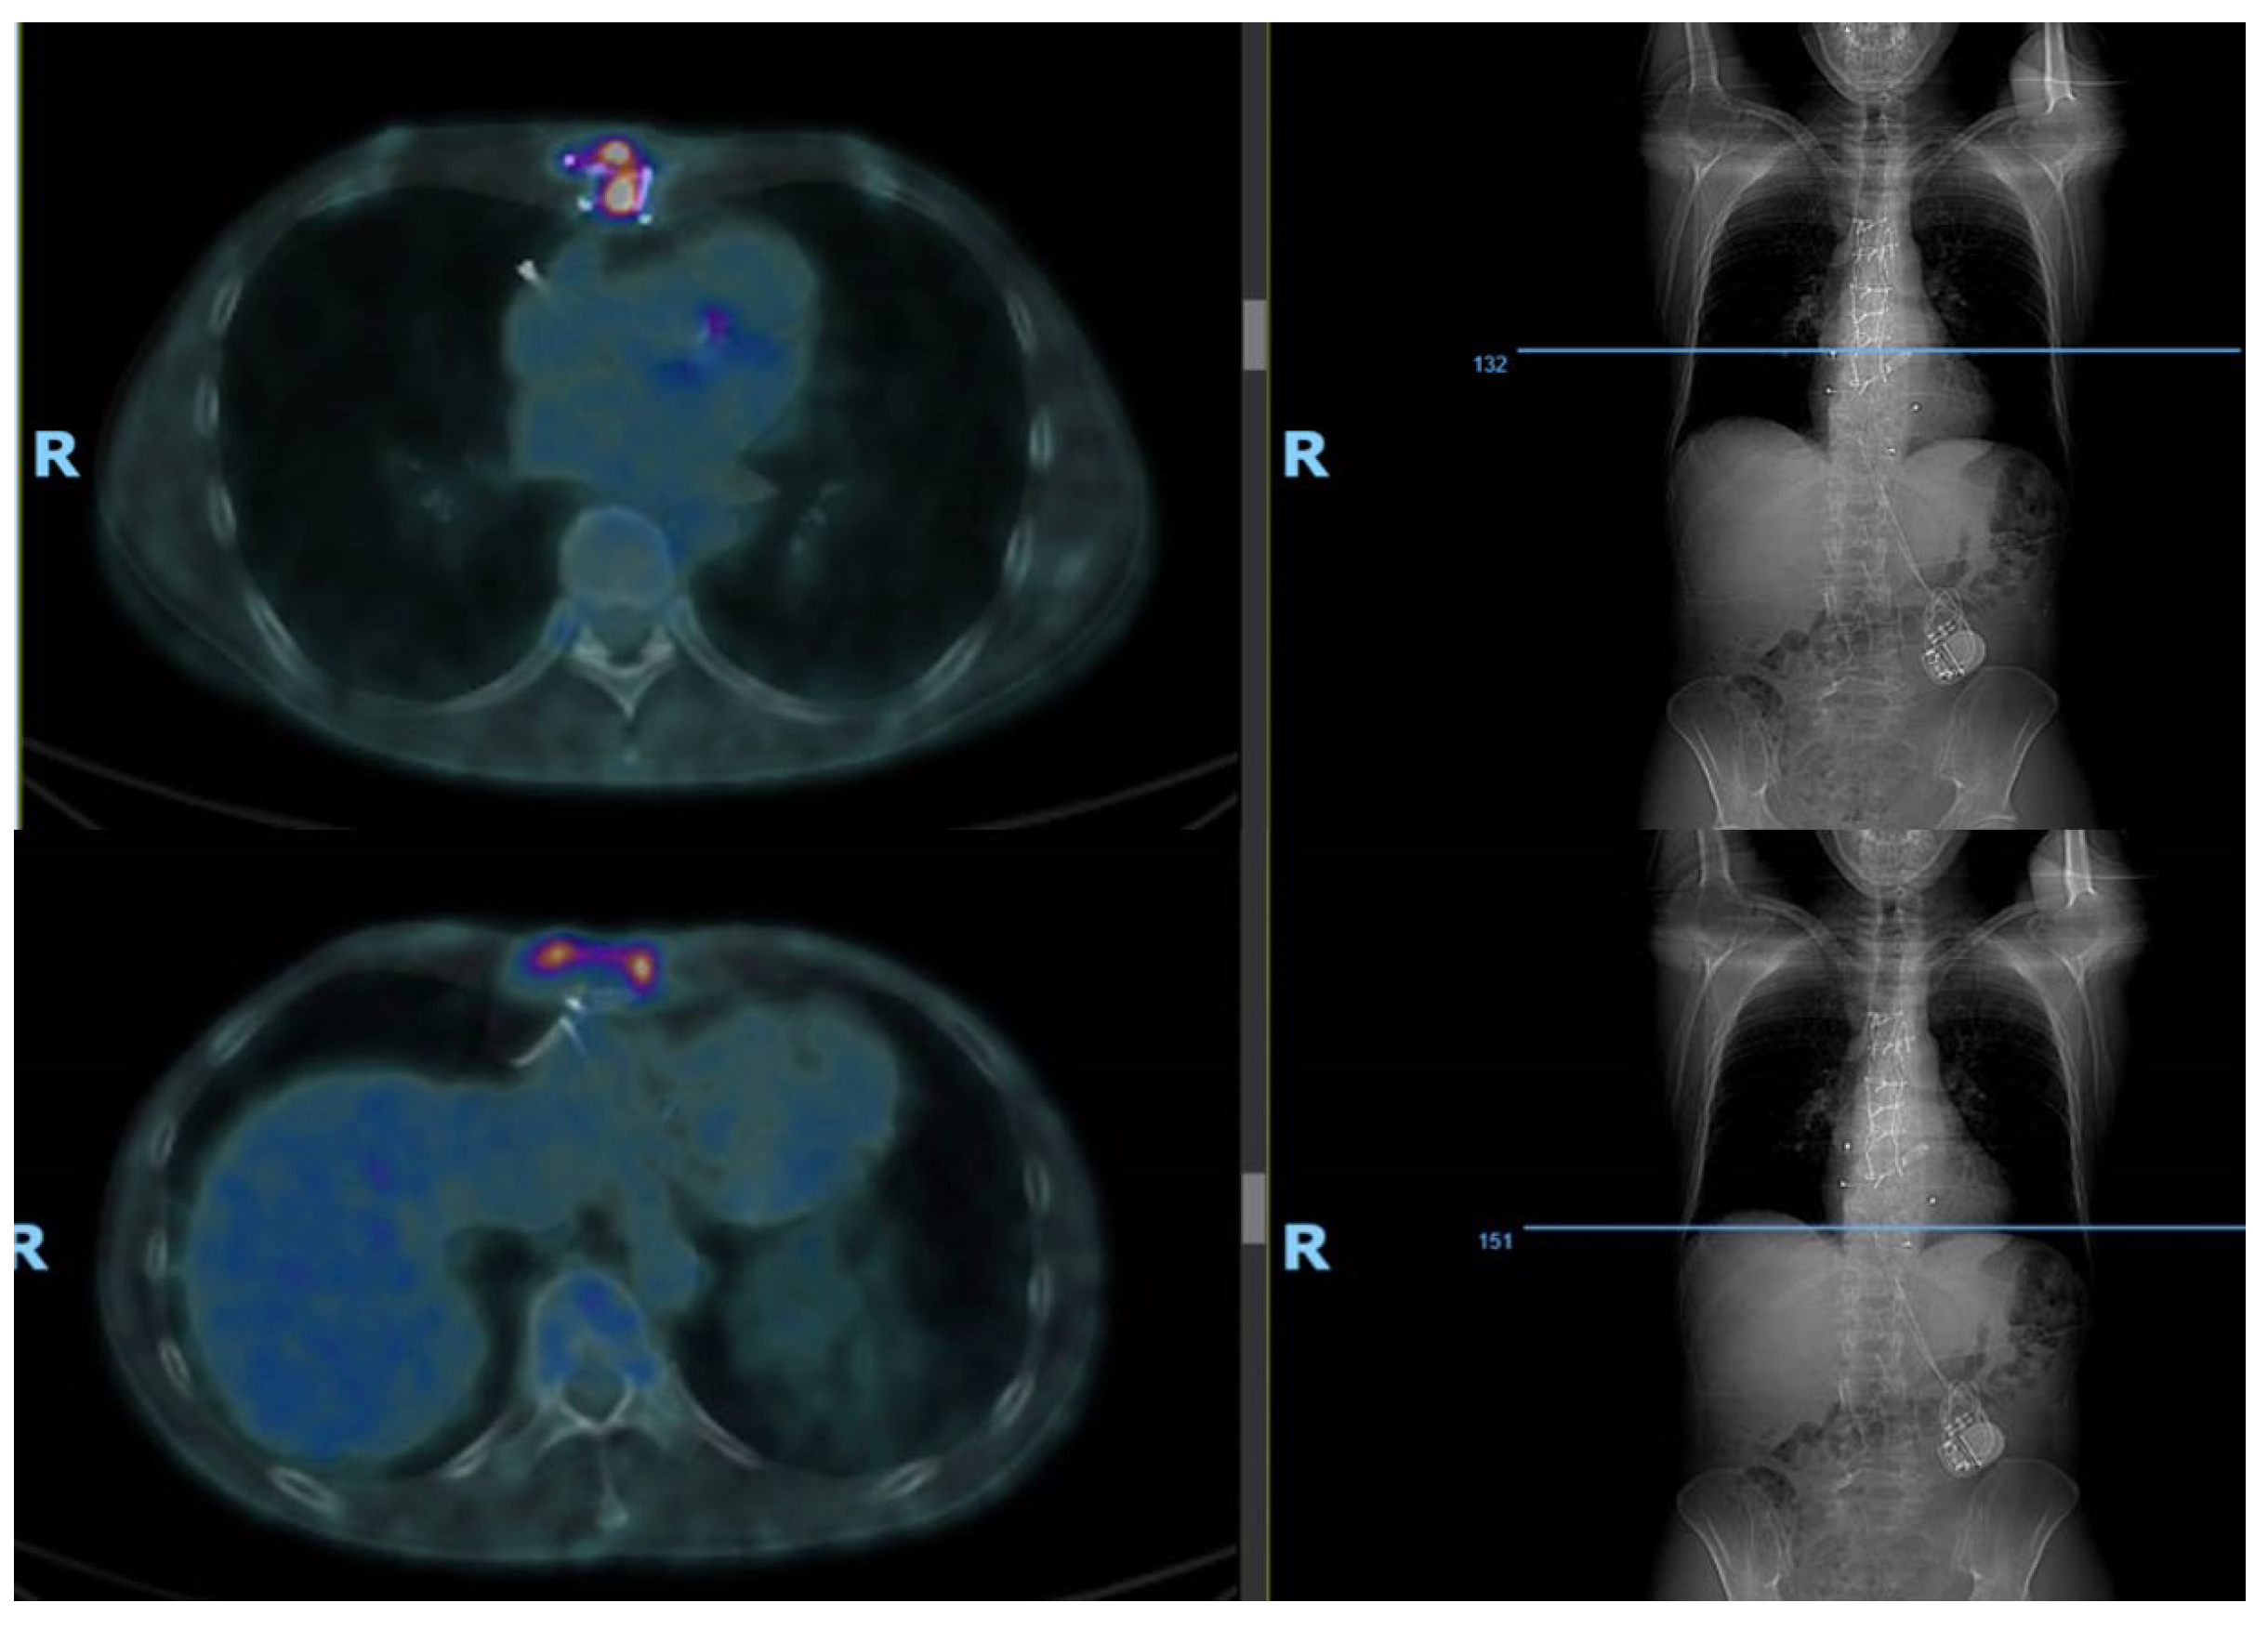

- Bleeker-Rovers, C.P.; Vos, F.J.; A Wanten, G.J.; Van Der Meer, J.W.M.; Corstens, F.H.M.; Kullberg, B.-J.; Oyen, W.J.G. 18F-FDG PET in detecting metastatic infectious disease. J. Nucl. Med. Off. Publ. Soc. Nucl. Med. 2005, 46, 2014–2019. [Google Scholar]

- Zhang, R.; Feng, Z.; Zhang, Y.; Tan, H.; Wang, J.; Qi, F. Diagnostic value of fluorine-18 deoxyglucose positron emission tomography/computed tomography in deep sternal wound infection. J. Plast. Reconstr. Aesthet. Surg. 2018, 71, 1768–1776. [Google Scholar] [CrossRef] [PubMed]

- Elsheikh, A.; Elazazy, M.; Elkaramany, M. Role of 18F-FDG PET-CT in Pre-Operative Planning of Surgical Debridement in Chronic Osteomyelitis. Indian J. Orthop. 2022, 56, 2237–2244. [Google Scholar] [CrossRef] [PubMed]